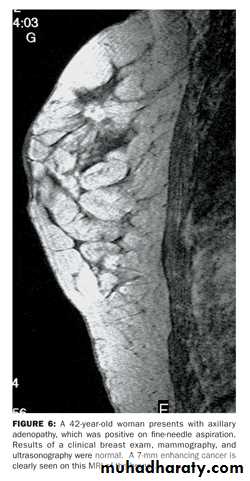

• a-mammography

• b-uls both for diagnosis and to guide biopsy

• c-magnetic resonance useful in symptomatic patient with breast implant where US is not diagnostic and also used in to detect local recurrence where US and mammography are un helpful